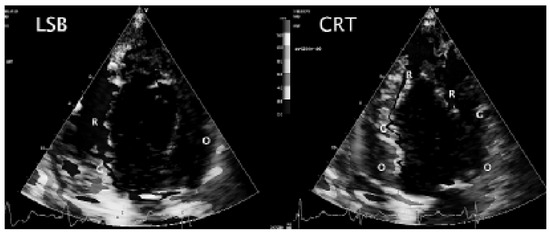

Biventricular pacing is an accepted therapy in patients suffering from terminal heart failure. Main obstacle however is the positioning of the left ventricular electrode via coronary sinus as well as its reliable fixation. This article describes in a...